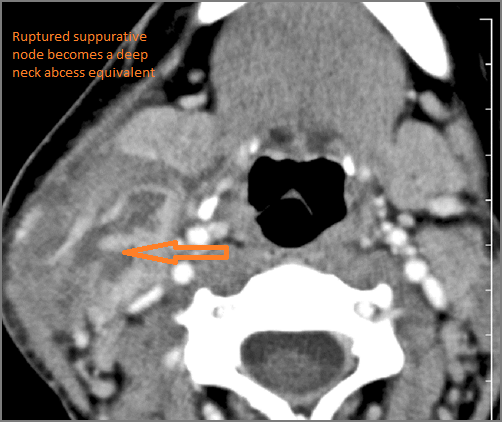

Cervical Lymph Nodes

If there is suppurative cervical adenopathy the purulent material outside the lymph node(s) capsule(s).